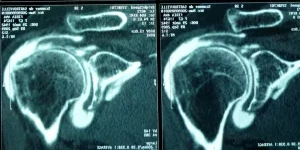

Le diagnostic repose sur un examen clinique complet réalisé par le médecin. Celui-ci permet d’évoquer une rupture de la coiffe (par exemple, des douleurs nocturnes) et d’éliminer d’autres pathologies possibles (fractures, capsulite rétractile, etc.). Un bilan complémentaire peut être nécessaire (radiographies, échographie, arthro-scanner, IRM, arthro-IRM, électromyogramme).

Lorsque la rupture est confirmée, l’étendue des lésions sera précisée en fonction de plusieurs critères : la localisation (dans le plan frontal ou sagittal), la taille de la rupture (complète ou partielle, un ou plusieurs tendons touchés), et la profondeur de la rupture. Le bilan servira aussi à évaluer la qualité osseuse et musculaire.